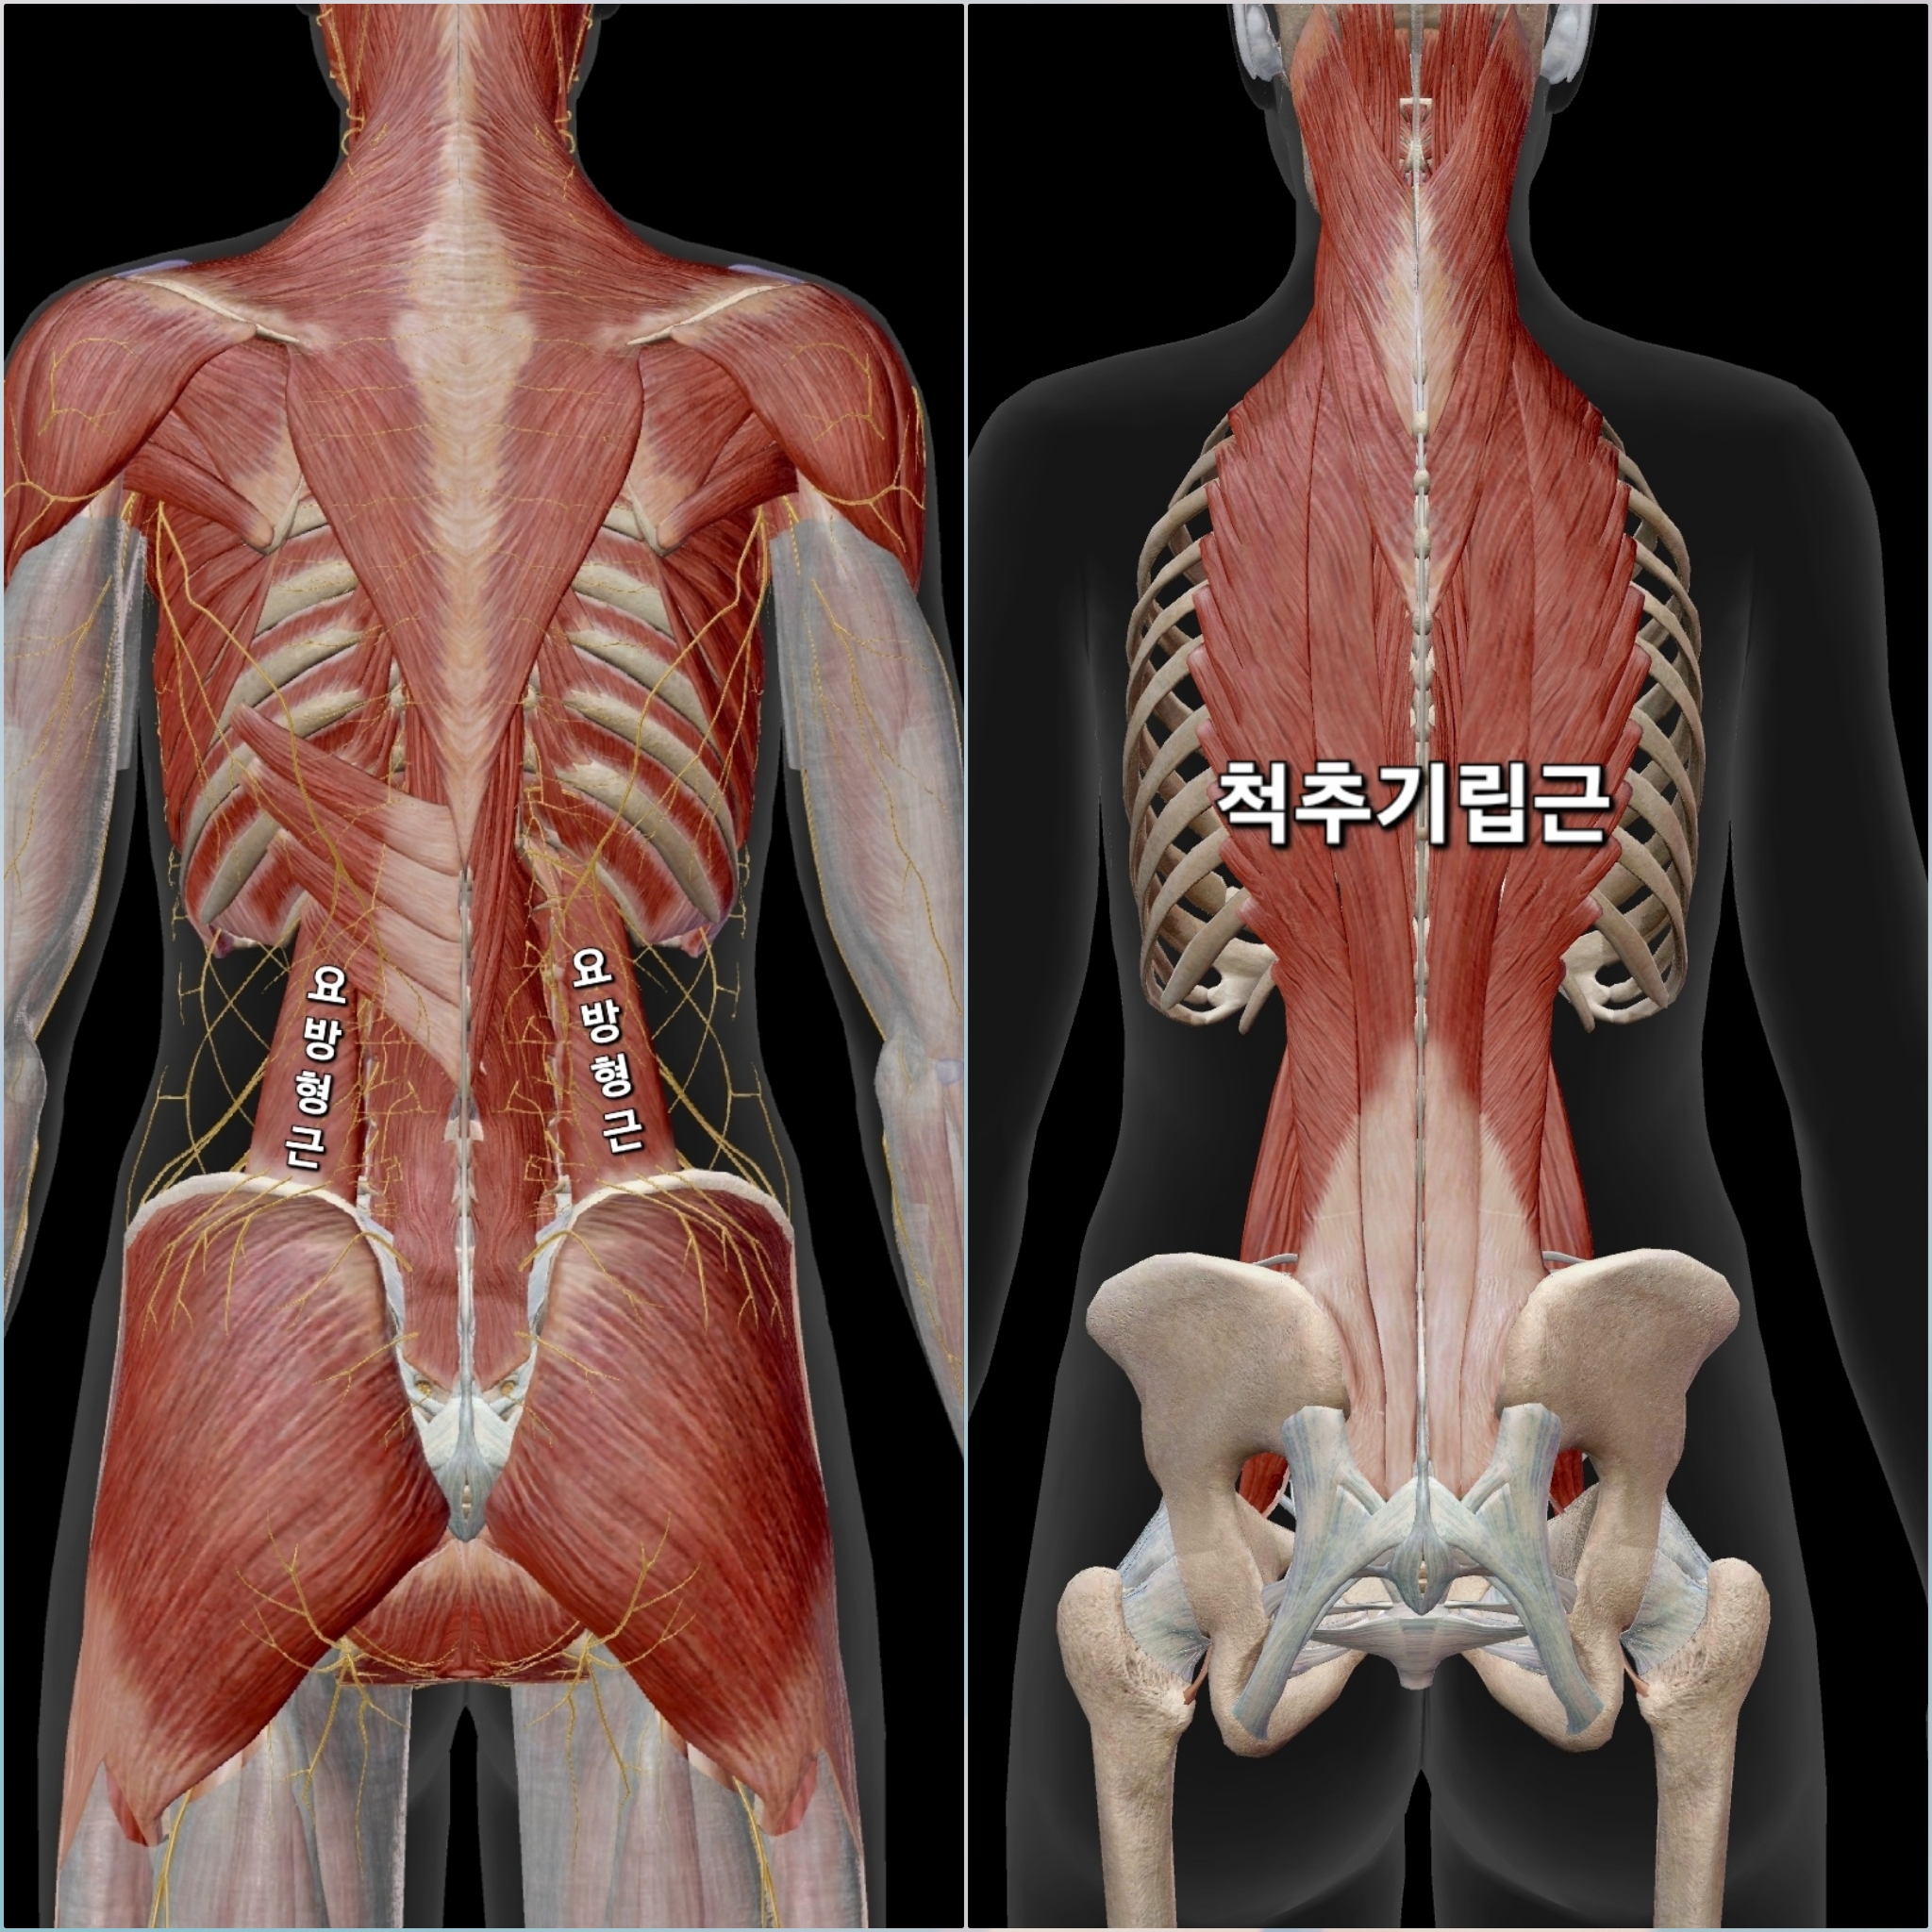

엉덩이 위쪽통증 (허리와 골반 연결 부위통증)

이유: 요방형근, 척추기립근의 과도한 긴장

ㆍ양반다리를 하면 척추·골반의 변화가 일어납니다 양반다리를 하면 골반이 뒤로 말려 기울어지는 후방경사가 일어나게 되는데 허리 따라서 둥글어지는 후만 상태가 됩니다 이때 양쪽 골반이 균등하게 바닥에 닿지 않고 한쪽이 더 눌리는 경우가 많습니다 몸이 한쪽으로 기울거나 척추 정렬이 흐트러질 수도 있습니다 이런 변화가 생기면 허리와 골반을 지탱하는 근육(요방형근, 척추기립근)이 긴장하면서 엉덩이 위쪽(허리-골반 연결 부위)에 통증이 발생할 가능성이 커집니다

ㆍ 요방형근은 골반과 허리(요추)를 연결하는 근육으로 골반이 한쪽으로 기울어질 때 보상 작용을 합니다 그리고 양반다리를 하면 골반이 뒤로 기울면서 요방형근이 늘어나면서 과긴장 됩니다 그리고 한쪽으로 기울어서 앉는 경우 요방형근이 비대칭적으로 긴장이 발생합니다 이 긴장이 지속되면 엉덩이 위쪽(허리와 골반 연결 부위)에서 둔하고 뻐근한 통증이 발생하게 됩니다

ㆍ 척추기립근은 허리를 곧게 펴는 역할을 하는데, 양반다리 자세에서 허리가 둥글어지면(후만) 이 근육들이 길어지면서 긴장합니다 특히 양반다리 시 허리를 세우려고 하면 척추기립근이 과하게 힘을 쓰면서 뻐근한 느낌이나 통증이 생길 수 있습니다

관련 문제 : 골반 틀어짐 / 요추전만 증가